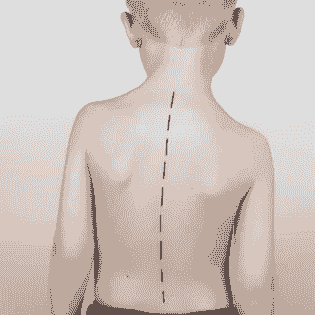

小童脊柱側彎

小童脊柱側彎最大機會出現的問題: -高低膊 -經常橋腳或盤膝坐 -坐直背脊會覺得容易攰 -走路很容易跌倒,容易受傷 -左右鞋底的磨損情況有所差異選擇日期與時間